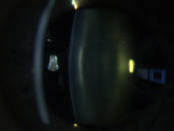

Katarakt („Grauer Star“)

Eine Katarakt (links) verursacht ein unscharfes Bild durch vermehrte Lichtstreuung. Ein Linsen - tausch (rechts) korrigiert den Abbildungsfehler.

Eine Katarakt (links) verursacht ein unscharfes Bild durch vermehrte Lichtstreuung. Ein Linsentausch (rechts)  korrigiert den Abbildungsfehler.